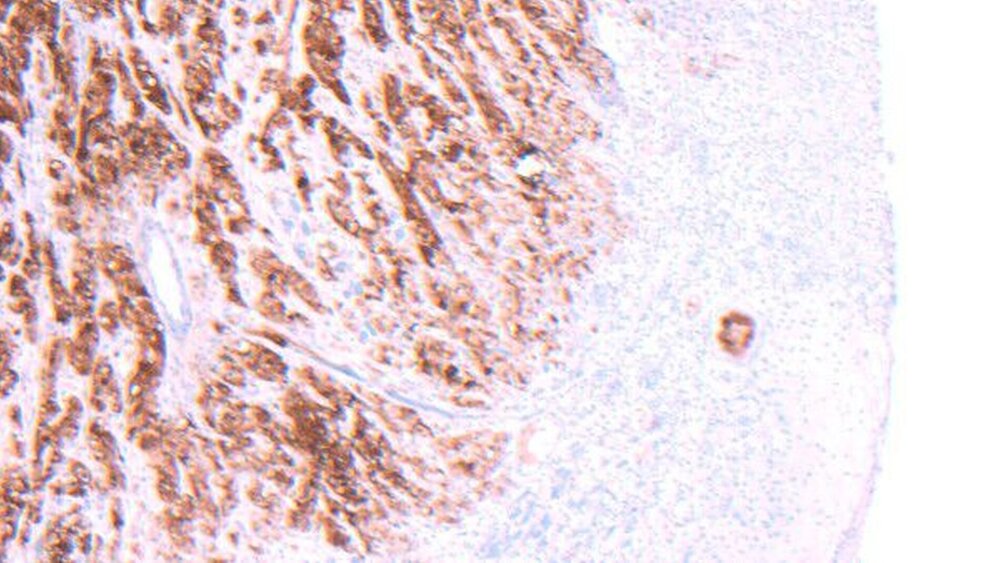

Zur Befundsicherung der intraoralen Neoplasie erfolgte eine Probeentnahme in Lokalanästhesie / Stand-by. Das Ergebnis der pathohistologischen Untersuchung bestätigte den Verdacht auf eine Metastase des bekannten epitheloiden Mesothelioms. Die immunhistochemische Untersuchung zeigte Tumorzellen, die eine starke Positivität für Calretinin aufwiesen, darüber hinaus einen starken Nachweis von Gesamtcytokeratin sowie Cytokeratin 5/6 (Abbildungen 2a und b).